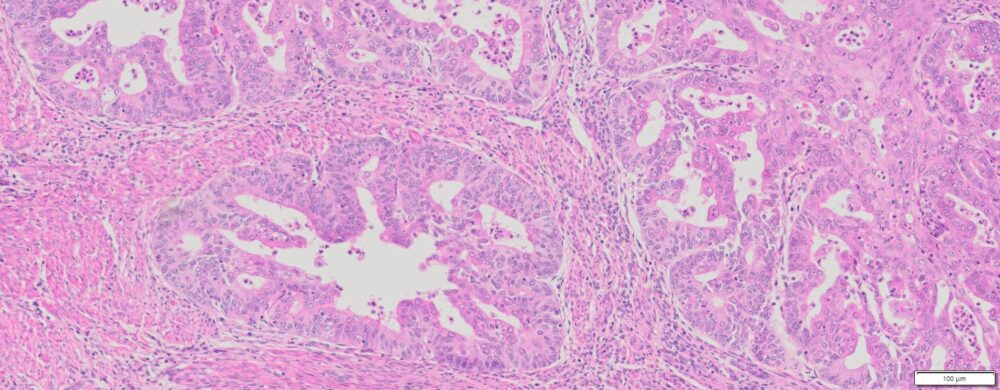

Description

| Organ& Tissue | Pathology Diagnosis | Gender/Age | % Tumor Area | Grade | TMN Stage | Biomarkers |

| Endometrial | Moderately differentiated endometrioid adenocarcinoma of the endometrium | Female/70 | 40% | 2 | T1bNxMx |